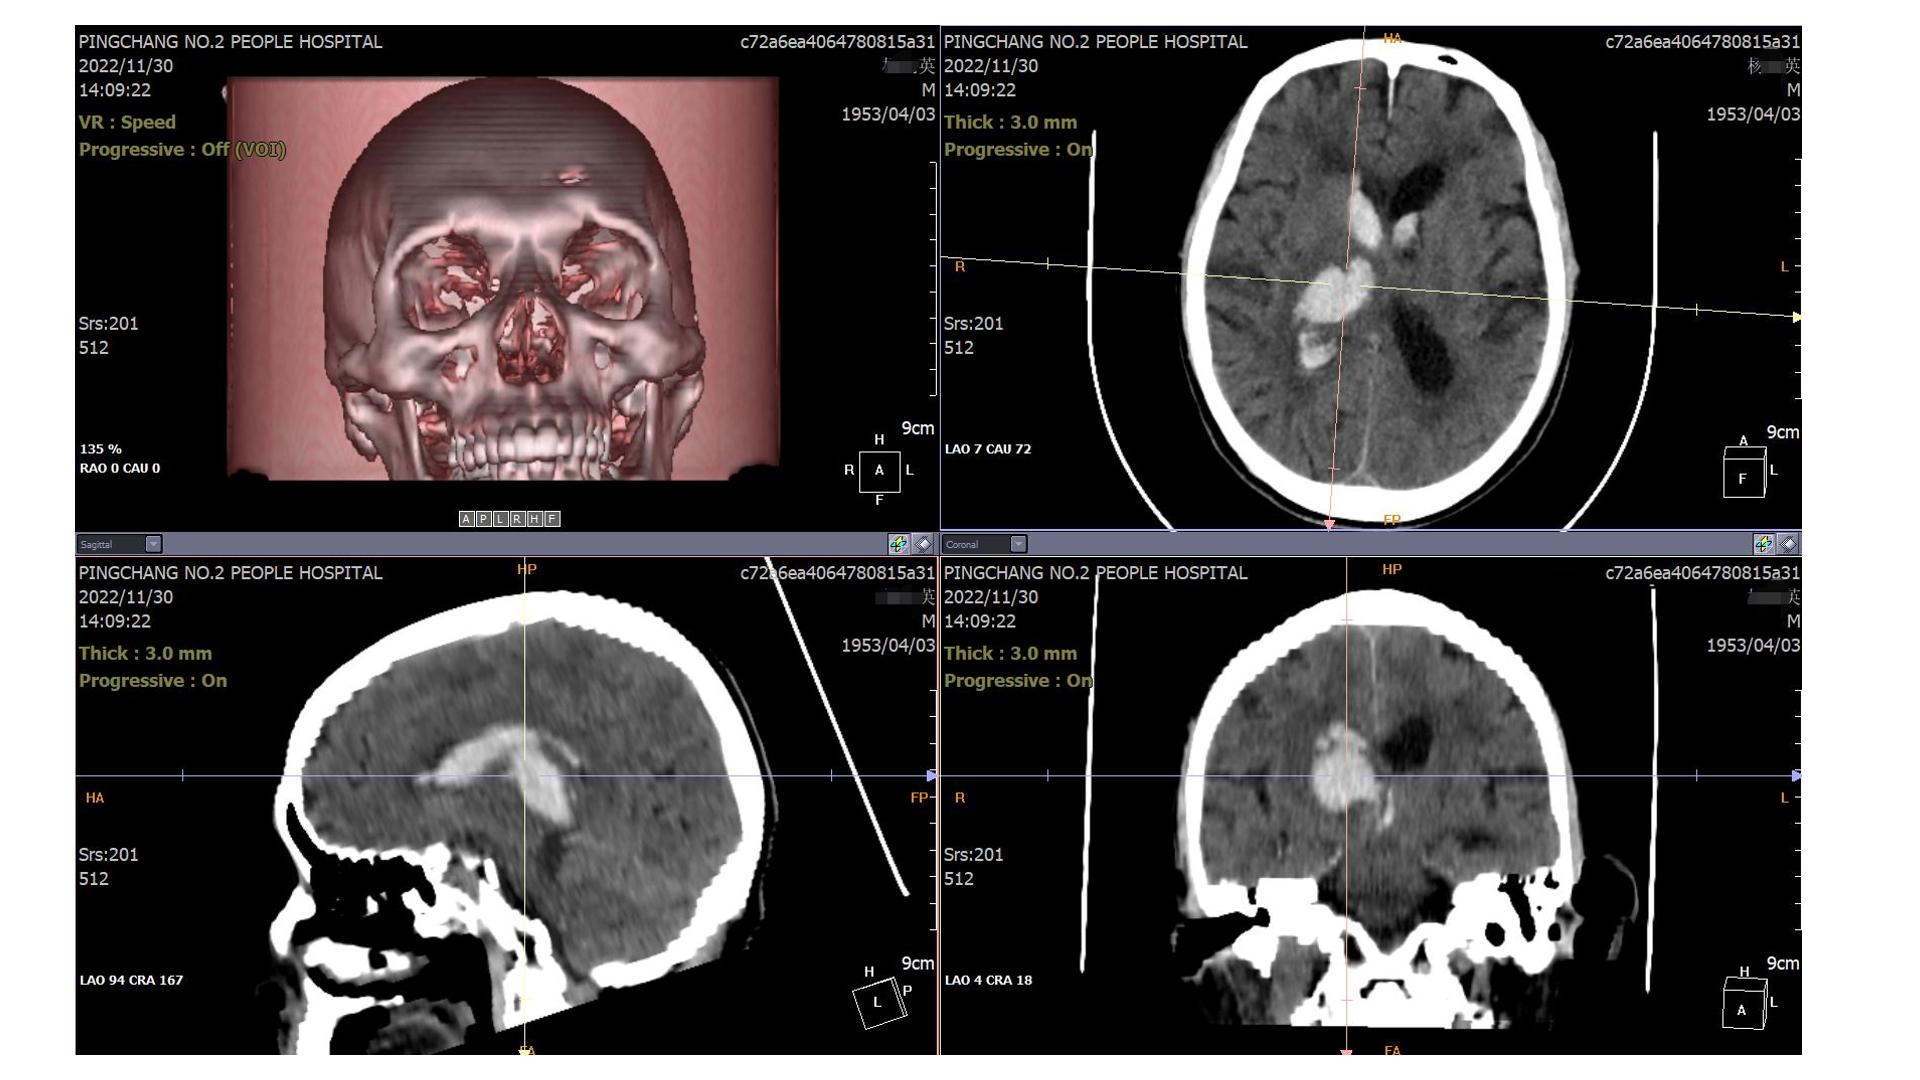

2022.11.30入院CT